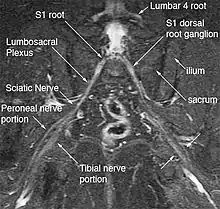

The most significant impact of magnetic resonance neurography is on the evaluation of the large proximal nerve elements such as the brachial plexus (the nerves between the cervical spine and the underarm that innervate shoulder, arm and hand),[9] the lumbosacral plexus (nerves between the lumbosacral spine and legs), the sciatic nerve in the pelvis,[10] as well as other nerves such as the pudendal nerve[11] that follow deep or complex courses.

Neurography has also been helpful for improving image diagnosis in spine disorders. It can help identify which spinal nerve is actually irritated as a supplement to routine spinal MRI. Standard spinal MRI only demonstrates the anatomy and numerous disk bulges, bone spurs or stenoses that may or may not actually cause nerve impingement symptoms.[12][13]

Use of magnetic resonance neurography is increasing in neurology and neurosurgery as the implications of its value in diagnosing various causes of sciatica becomes more widespread.[25][26] There are 1.5 million lumbar MRI scans performed in the US each year for sciatica, leading to surgery for a herniated disk in about 300,000 patients per year. Of these, about 100,000 surgeries fail. Therefore, there is successful treatment for sciatica in just 200,000 and failure of diagnosis or treatment in up to 1.3 million annually in the US alone. The success rate of the paradigm of lumbar MRI and disk resection for treatment of sciatica is therefore about 15%(Filler 2005). Neurography has been applied increasingly to evaluate the distal nerve roots, lumbo-sacral plexus and proximal sciatic nerve in the pelvis and thigh to find other causes of sciatica. It is increasingly important for brachial plexus imaging and for the diagnosis of thoracic outlet syndrome.[27] Research and development in the clinical use of diagnostic neurography has taken place at Johns Hopkins, the Mayo Clinic, UCLA, UCSF, Harvard, the University of Washington in Seattle, University of London, and Oxford University (see references below) as well as through the Neurography Institute. Recent patent litigation concerning MR Neurography has led some unlicensed centers to discontinue offering the technique. Courses have been offered for radiologists at the annual meetings of the Radiological Society of North America (RSNA), and at the International Society for Magnetic Resonance in Medicine and for surgeons at the annual meetings of the American Association of Neurological Surgeons and the Congress of Neurological Surgeons. The use of imaging for diagnosis of nerve disorders represents a change from the way most physicians were trained to practice over the past several decades, as older routine tests fail to identify the diagnosis for nerve related disorders. The New England Journal of Medicine in July 2009 published a report on whole body neurography using a diffusion based neurography technique.[28] In 2010, RadioGraphics - a publication of the Radiological Society of North America that serves to provide continuing medical education to radiologists - published an article series taking the position that Neurography has an important role in the evaluation of entrapment neuropathies.[29]